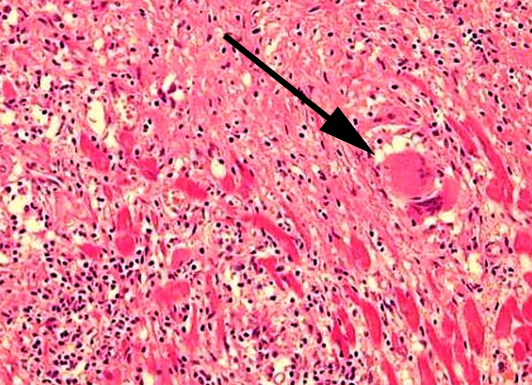

Sehen Sie nachfolgend einige Bilder, auf denen verschiedene Untersuchungsergebnisse gezeigt werden:

Besondere Entzündungsform des Herzmuskels (Sarkoidose). Die Entzündung erkennt man am Auftreten kugeliger Gebilde (Pfeil) im Herzmuskel..